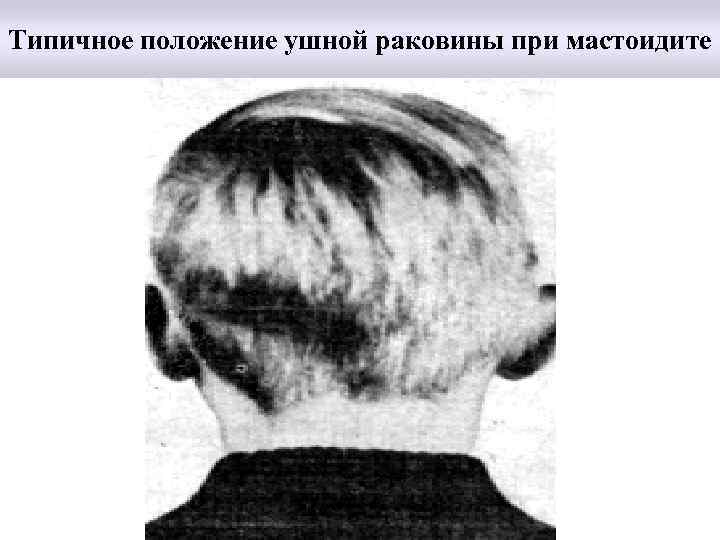

Типичное положение ушной раковины при мастоидите